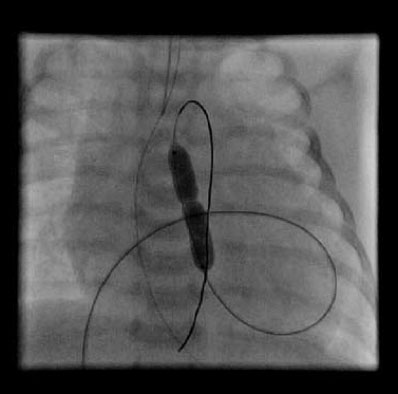

Image of a pulmonary valvuloplasty

Depending on the location of the narrowing area, they can be subvalvular (if they are localized, they are usually due to an impeller. It can that be the entire outflow tract of the left ventricle, encompassing the aortic valve ring, which complicates its treatment); valvular or supravalvular (characteristic association with the William’sSyndrome, which affects the entrance of the coronary arteries). Their treatment will be determined by the degree of narrowness and its location. In valvular forms the first thing is to perform an aortic valvuloplasty (using balloon dilation by catheterization, as seen in the next diagram) and wait for the child to grow, eventually placing a mechanical prosthesis when feasible (ideally after growth is complete, from around 12 years old).

Image of an aortic valvuloplasty